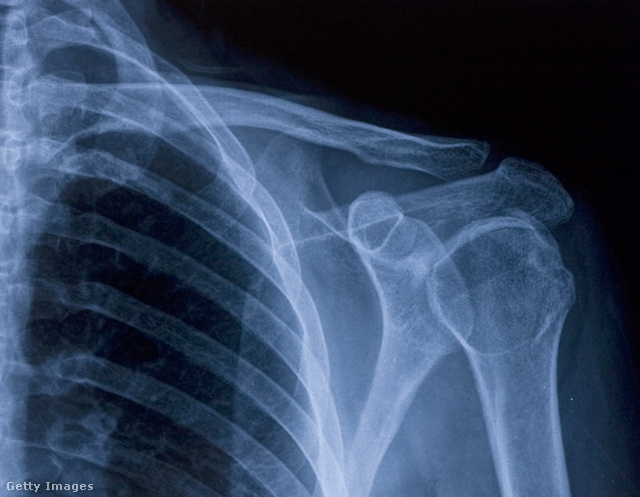

A vállunkat egyébként alapvetően három csont alkotja: a felkarcsont, a lapocka és a kulcscsont. A teljes mozgás nem jöhetne létre ezek ízesülései nélkül, a vállövünkön így összesen öt ízület található (ebből kettő valódi anatómiai ízület).

A felkarcsont (humerus) feje és a lapocka (scapula) ízületi árka alkotja a tényleges vállízületet (articulatio humeri). Az ízületi árok (vápa), amelybe illeszkedik a felkarcsont feje, igen sekély, maga az ízületi tok pedig bő – ez azt a célt szolgálja, hogy az ízület számos irányba mozgatható legyen. Hogy mégis egyben marad, az az ízületet körülvevő izmoknak és szalagoknak köszönhető, valamint a vápában egy porcos gyűrűnek (labrum), amely mélyíti az árkot.

A lapockáról négy olyan izom ered, amelyek a felkarcsont fejét köpenyszerűen körbevéve stabilizálják az ízületet és lehetővé teszik a váll rotációs mozgását. Ez a rotátorköpeny, ennek a felkar oldalirányú emelése és előre-hátra forgatása a feladata, valamint jelentős szerepet játszik az ízület stabilizálásában. Ha valamilyen behatásra az ízületi fej ki akarna mozdulni az ízületi árokból, a ficam megakadályozása is a rotátorköpeny feladata.

A vállízület gömbízület, ami három tengely mentén képes mozgásokat létrehozni: hajlítást és feszítést, távolítást-közelítést, az imént említett forgatást (rotáció), illetve körzést.